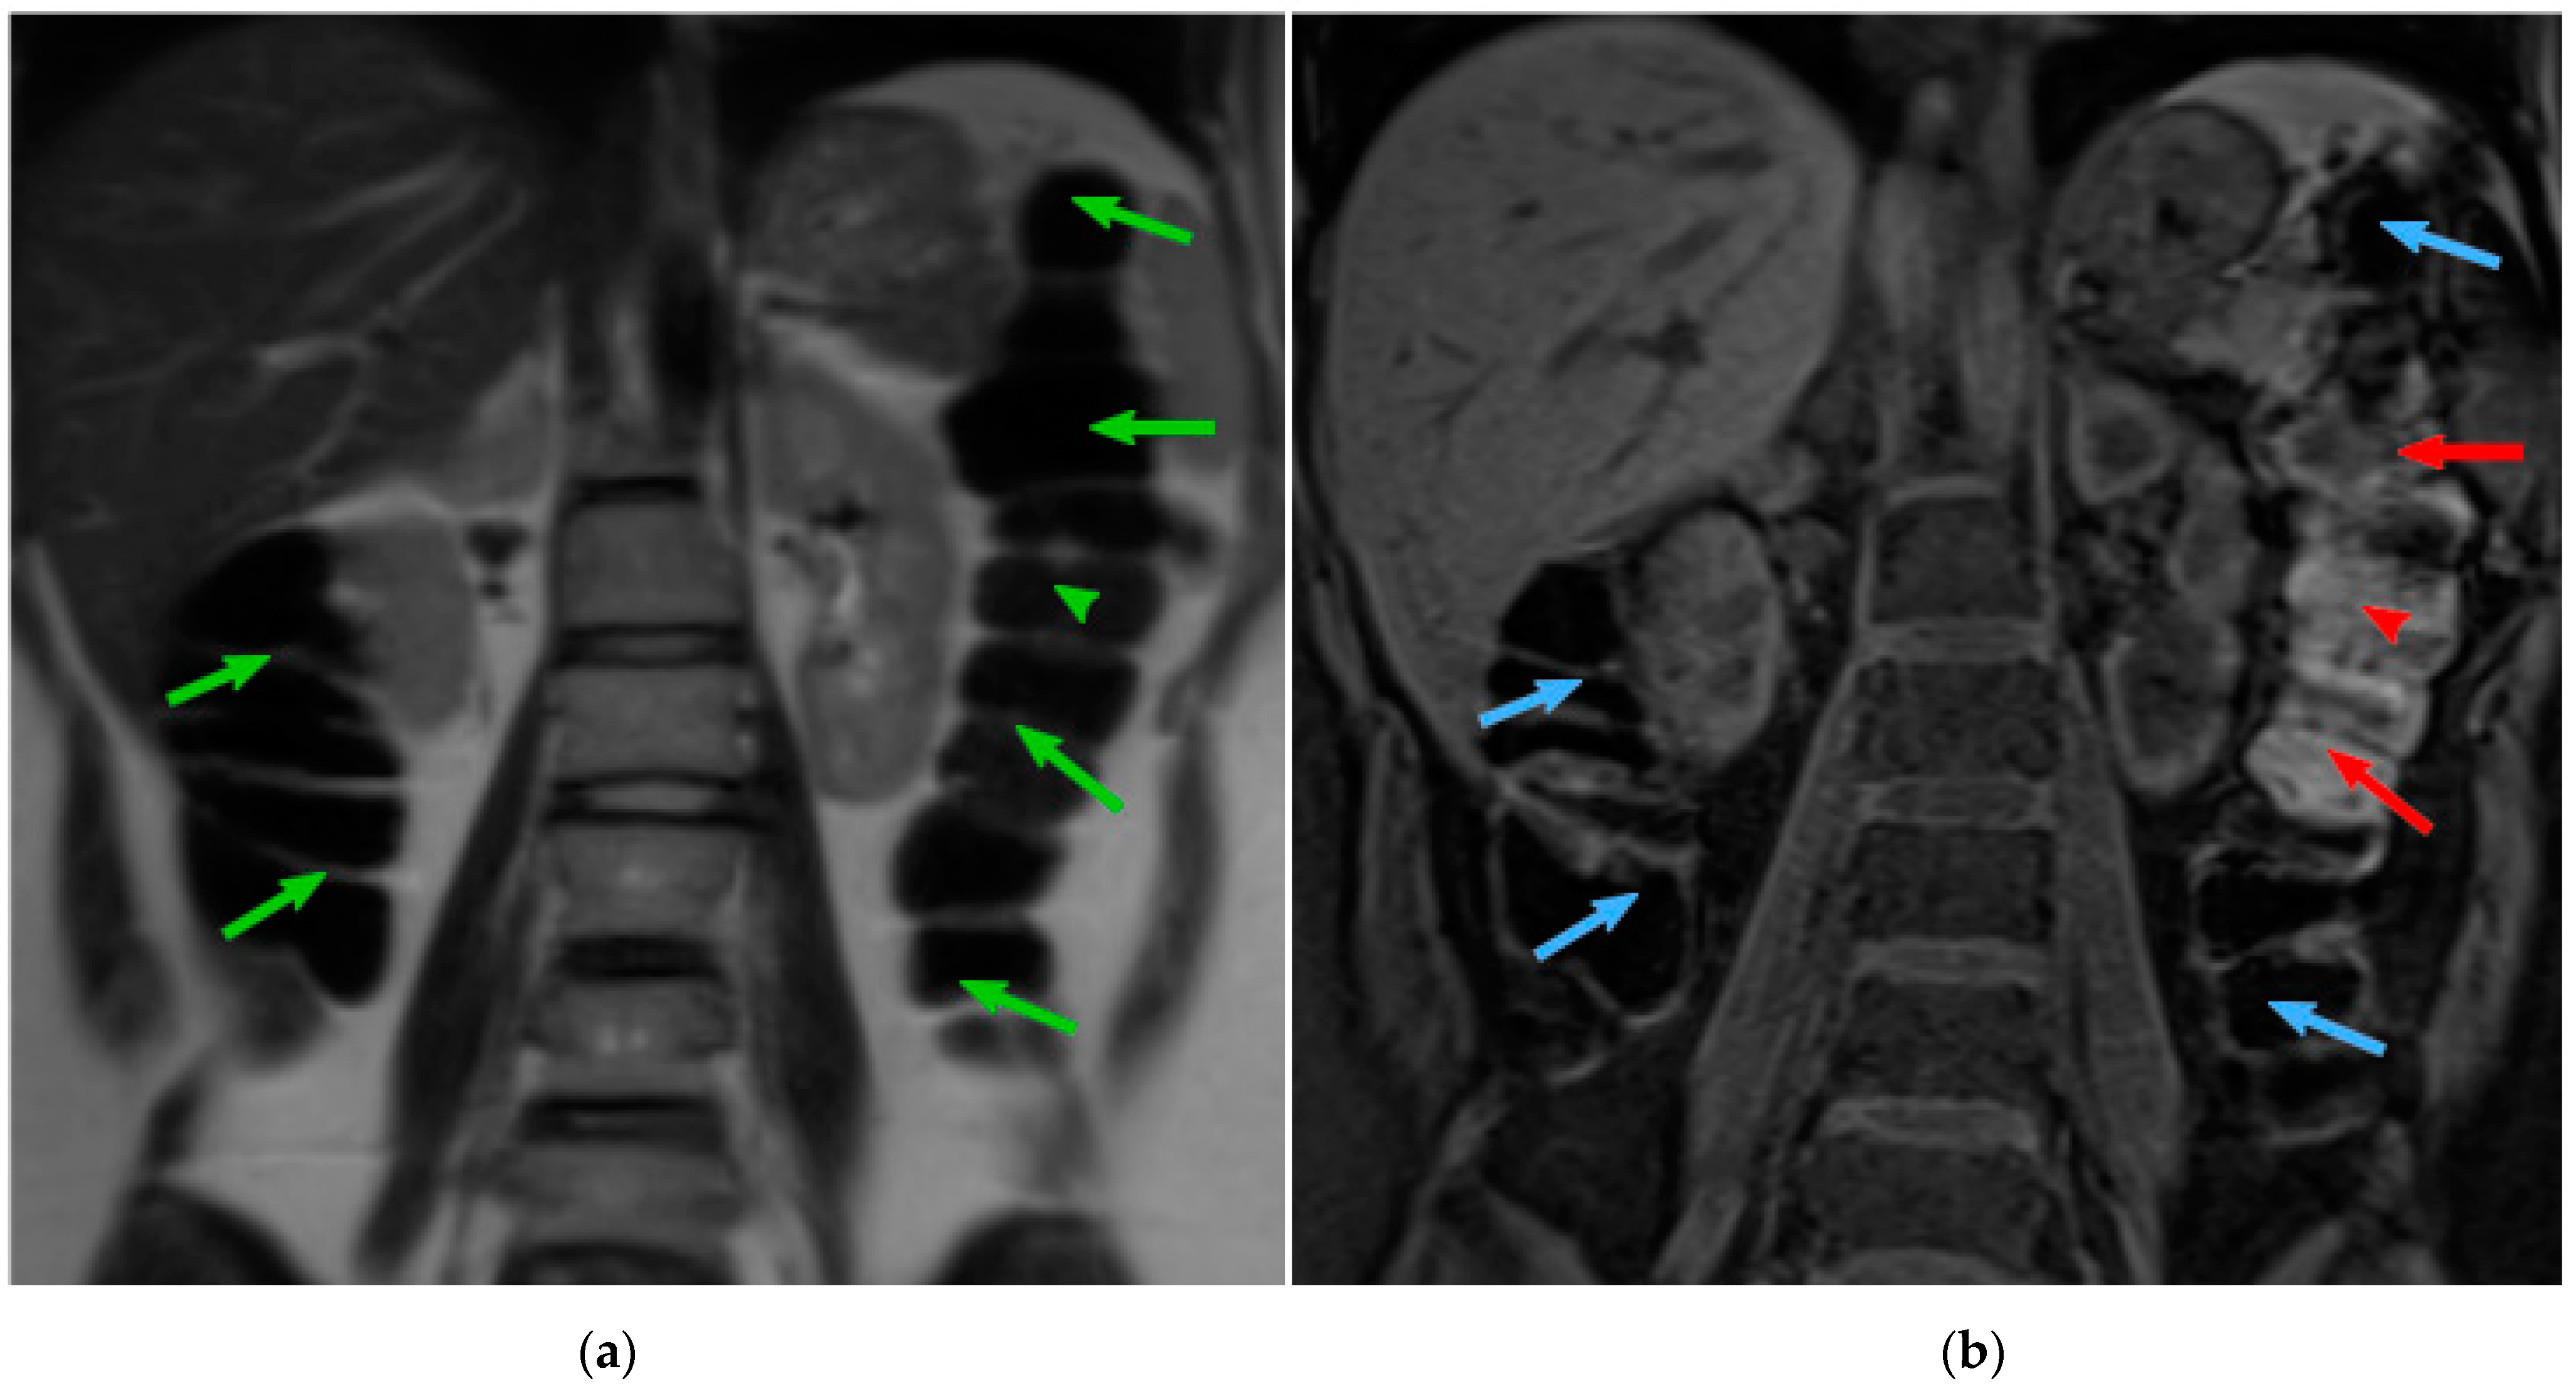

Figure 1.

(a) MRI T2 coronal slice showing ascending colon and descending colon (green arrows). (b) The same area in the T1-FS modality. Arrows are colorized depending on the contents: blue arrows point to gas and red to feces. Courtesy of [7].

About half of the patients in gastroenterological practice complain of digestive symptoms without detectable abnormalities by conventional diagnostic tests. In a large proportion of these patients, specifically those with intestinal functional disorders, their symptoms seem related to colonic dysfunction and abnormal intraluminal contents; however, the evaluation of the volume and distribution of solid and gas content in the colon is fraught with methodological constrains. Abdominal imaging by means of computer tomography (CT) has shed some light into the physiology of colonic handling of contents and disease [1,2,3,4,5]. Magnetic resonance imaging (MRI) has recently become an alternative technique to CT, since it provides an appropriate visualization of soft tissues while avoiding the exposure to ionizing radiation used in CT [6]. The MRI acquisition technique allows the modification of the signal emitted to acquire the different tissues presented in the body. The MRI modalities commonly used for the analysis of colonic content are T2-weighted (T2) and T1-weighted fat-SAT (T1-FS). However, those techniques, by themselves, do not allow the measurement of the colonic content. T2 sequence offers an optimal visualization of the colon boundaries, contrasting the colon lumen (dark voxels) against the fat around the colon (bright voxels) (Figure 1a). T1-FS sequence (Figure 1b) provides visual discrimination of the colonic content: feces are bright regions, while colonic gas is dark. Therefore, the information found in T1-FS and T2 images is complementary and both modalities are required to obtain a quantitative assessment of colonic morphology and content. To study the gut in normal conditions, it is necessary to acquire the abdominal images without preparation, e.g., administration of drugs or contrast.

In general, MRI scans are harder to segment than CT scan images due to the lack of fixed correspondence between tissues and intensities and the incidence of noise and artifacts on the images [8]. T2 modality displays the colon as a dark region contrasted with bright surrounding fat, but its appearance may suffer large intensity and texture variations along its tract, mainly caused by the presence of colonic content. Regarding T1-FS, this modality allows for the proper discrimination of fecal content: feces are bright regions while colonic gas is dark. However, fat tissues are also dark, almost indistinguishable from the adjacent colon gas. In consequence, colonic boundaries in T1-FS are not visible in regions with little presence of faces. Since clinical research involves numerous studies to be analyzed, and current colon segmentation algorithms are time-consuming for the specialists, the clinical practice would benefit from a higher degree of automation of colon segmentation algorithms.